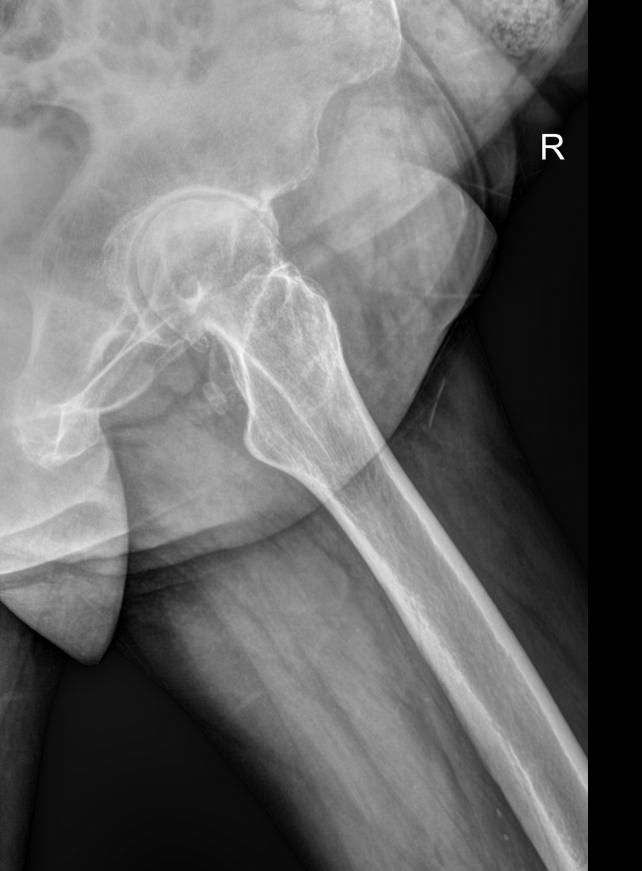

Рентгенография ― один из наиболее информативных методов диагностики патологий тазобедренных суставов. Это доступная, распространенная и неинвазивная диагностика, несущая минимальное количество ионизирующего излучения. В результате исследования можно обнаружить изменения, как травматические, так и воспалительного характера, происходящие с самыми крупными сочленениями костей в организме человека.

• Состояние суставных щелей, их симметричность и особенности;

• Соответствие вертлужных впадин головкам бедренных костей;

• Структуру костной ткани и патологические изменения в ней в области суставов;

• Врожденные аномалии, например, дисплазию;

• Переломы и вывихи;

• Новообразования.